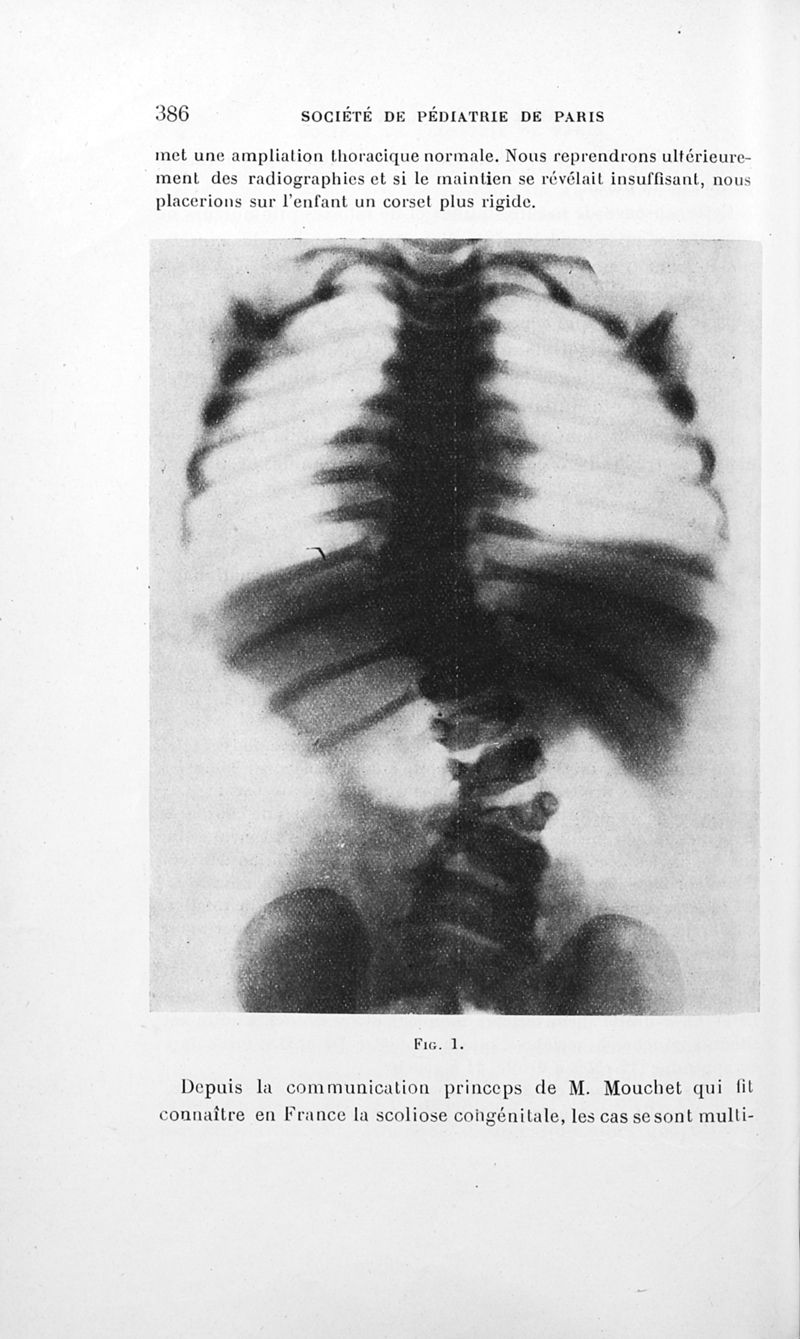

Bulletins de la société de pédiatrie de Paris

Tome vingt-septième. - Paris : Masson et Cie, 1929.